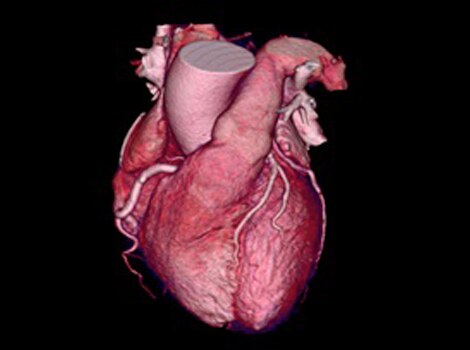

3D Heart

Visualize the anatomical structures and vascularity of the heart with a bright blood, 3D sequence.

Read More

Visualize the anatomical structures and vascularity of the heart with a bright blood, 3D sequence. Read More